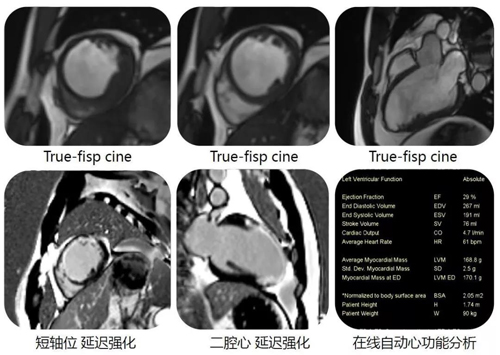

7、心脏磁共振检查

利用多层多通道体部专用线圈以及快速扫描序列技术,可对各种心脏大血管病变及心功能测定做出准确影像诊断。

9.jpg